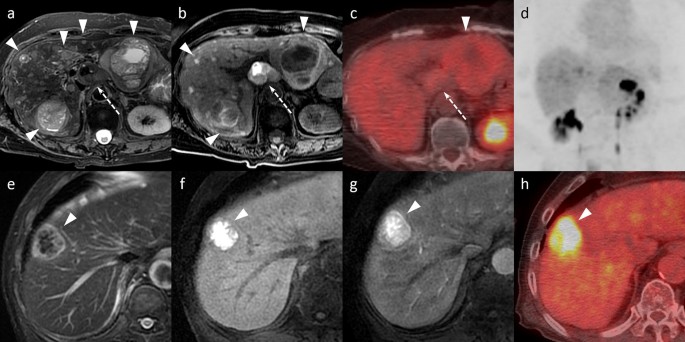

- ონკოლოგია

- დიაგნოსტიკა

ტეგი: სხივური თერაპია